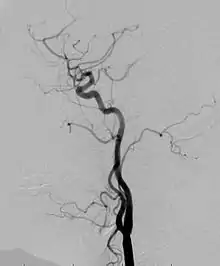

Angiogram: an angiogram can also be ordered to get a detailed look at the blood vessels in the affected or overgrown limb. In this test a physician injects a dye into the blood vessels that will help see how the blood vessels are malformed.[22]